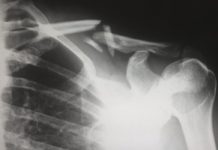

Se identifican los genes que determinan el riesgo de padecer osteoporosis

Se identifican los genes que determinan el riesgo de padecer osteoporosis y las posibles fracturas óseas. Un estudio reciente realizado por investigadores de la Universidad de Barcelona y del Hospital del Mar permite identificar los genes asociados con una mayor susceptibilidad a sufrir osteoporosis y fracturas óseas. Se trata de un avance científico de gran importancia ya que permite progresar en el campo de nuevas terapias.